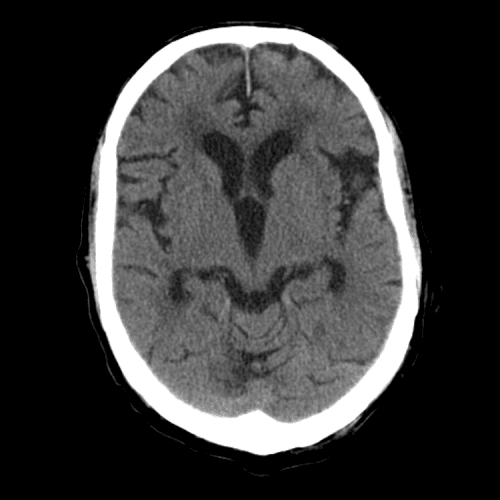

PICA infarct